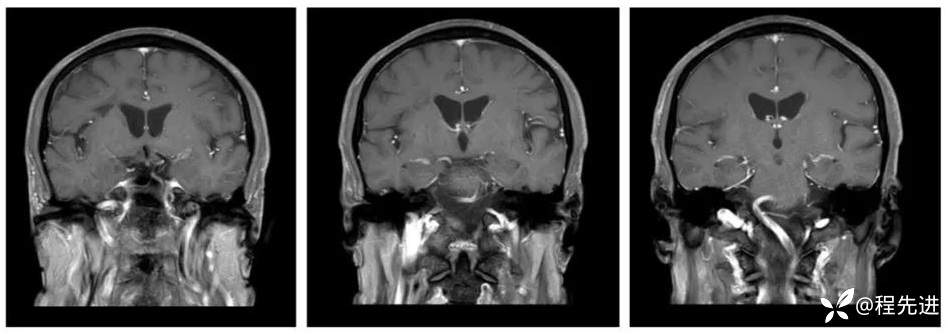

MRI平扫+增强:

T2、T1:

T1增强冠状位: